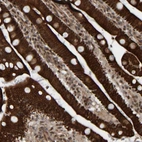

Immunohistochemical staining of human duodenum shows strong cytoplasmic positivity in glandular cells.